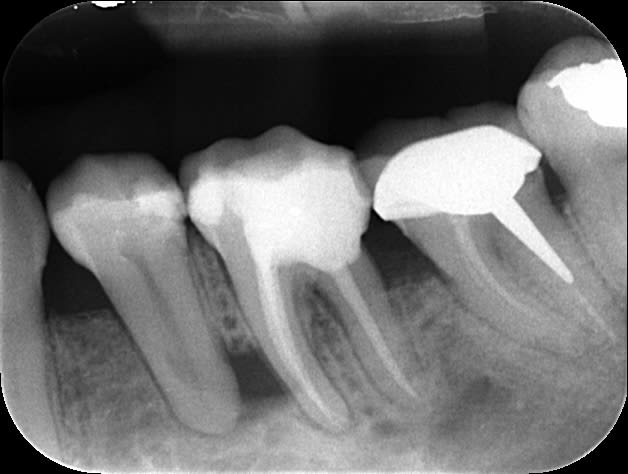

Photo 1:radio finale endo faite en juillet, difficile pour l'anesthésie j'ai dû en rajouter 1 carpule en intralig.

Photo 2 : Bref je revois la patiente fin Aout à mon retour et elle me dit qu'elle à toujours mal même si ça va mieux 2 : gencive bien gonflée entre 36 et 35, 35 douloureuse mais vitale.